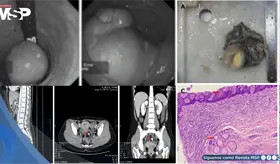

Las imágenes sugirieron un tumor con hueso, grasa y tejido cerebral dentro del recto, confirmando un diagnóstico poco común que solo se documenta en uno de cada 35.000 a 40.000 casos a nivel mundial.